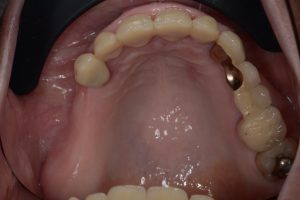

A paciente Monique, de 72 anos, apresentou-se com uma situação clássica de extremidade livre do 14 ao 17. Sua principal solicitação era o fechamento rápido e fixo do espaço esteticamente comprometido (Fig. 1). Devido a uma doença autoimune (síndrome de Sjögren), sua produção de saliva era limitada, o que reduzia a inibição natural do crescimento bacteriano oral pelo corpo e aumentava o risco de complicações na cicatrização de feridas. A paciente estava ciente desse fato e, portanto, solicitou explicitamente um procedimento cirúrgico minimamente invasivo que evitasse medidas complexas de aumento.

O diagnóstico padrão com escaneamento intraoral e CTCB (Fig. 3 escaner intraoral e Fig. 4 CTCB) mostrou disponibilidade óssea reduzida nas regiões 15 a 17, mas suficiente para a colocação imediata do implante. O dente 13, restaurado endodonticamente, apresentava uma obturação radicular que se estendia claramente além do ápice, juntamente com periodontite periapical. Em consulta com o paciente, foi decidido remover o dente.